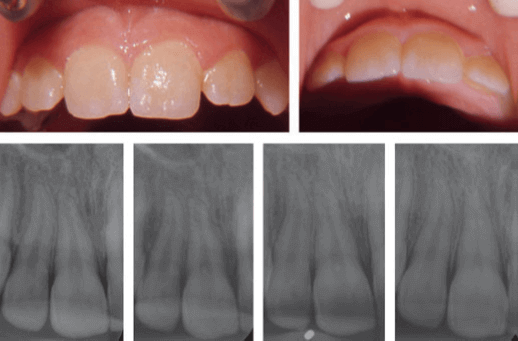

La concusión y la subluxación se describieron por primera vez en 1972 como tipos distintos de lesión del ligamento periodontal y de la pulpa. Una concusión se define como una lesión de las estructuras de soporte del diente sin aflojamiento ni desplazamiento anormales, pero con una reacción marcada a la percusión. Una lesión por subluxación se define como una lesión en las estructuras de soporte dental con aflojamiento anormal, pero sin desplazamiento dental.

Se supone que la etiología de una lesión por conmoción es un impacto menor en el diente, en el que la energía liberada solo ha provocado edema o sangrado y, en ocasiones, pequeñas laceraciones en el ligamento periodontal. La etiología de la subluxación es probablemente el resultado de un impacto menor en el ligamento periodontal, en el que la energía liberada provoca sangrado, edema y desgarro de las fibras del ligamento periodontal, lo que conduce a un aflojamiento anormal. Un estudio experimental en ratas ha demostrado estos cambios menores en el ligamento periodontal, así como sangrado en la capa odontoblástica cerca del foramen apical en dientes con concusiones y subluxaciones. Estudios previos sobre concusiones y subluxaciones se han centrado principalmente en la curación de la pulpa y las complicaciones pulpares.

La cicatrización periodontal tras una concusión y una subluxación solo se ha mencionado brevemente en relación con estudios previos sobre el pronóstico de los dientes permanentes luxados, que se centraban en el desarrollo de necrosis pulpar. La relación entre la reabsorción relacionada con la reparación y los dientes con lesiones múltiples podría estar relacionada con un diagnóstico insuficiente de la gravedad de la lesión por luxación en casos con múltiples dientes traumatizados. La diferencia entre una concusión y una lesión por subluxación se basa en una decisión subjetiva. Si varios dientes están involucrados en la lesión, la atención del examinador puede centrarse en los dientes con un diagnóstico más grave, por ejemplo, extrusión, luxación lateral, fractura alveolar o avulsión, y una subluxación puede, en este caso, clasificarse como una conmoción. En los dientes con una lesión por subluxación, la reabsorción relacionada con la reparación solo se produjo en los dientes con ápices cerrados y, en dos de los tres casos, también se observó necrosis pulpar. En estos casos, es posible que la reabsorción no esté causada por el traumatismo, sino que esté relacionada con la curación de una periodontitis apical derivada de la infección en el conducto radicular.

El bajo riesgo de reabsorción relacionada con la reparación indica que el daño causado por el traumatismo debió de ser muy limitado. De hecho, la frecuencia de reabsorción relacionada con la reparación no fue mayor en los dientes con lesiones por subluxación que en los dientes con lesiones por conmoción. En estudios de reimplantación en monos, la reabsorción relacionada con la reparación se ha localizado en áreas con lesiones moderadas del ligamento periodontal. También es interesante que los estudios histológicos de dientes humanos «normales» mostraron que la reabsorción relacionada con la reparación se encontró en casi todos los dientes. Estas áreas de reabsorción eran generalmente superficiales, lo que implica que no pueden diagnosticarse radiográficamente. En conclusión, el riesgo de complicaciones en la cicatrización periodontal tras lesiones por concusión y subluxación en la dentición permanente es muy bajo.